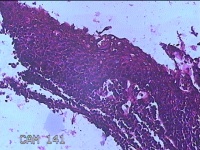

性别

女

年龄

6岁

临床诊断

1.阻塞性睡眠呼吸暂停综合征 2.腺样体肥大 3.扁桃体肥大 4.变应性鼻炎

一般病史

鼻塞、张口呼吸伴睡眠呼吸暂停半年余。

标本名称

双侧扁桃体

大体所见

灰白粉红色扁桃体4x3x0.8cm两个,表面均有部分糜烂,切面灰白粉红色,结节状,质软。